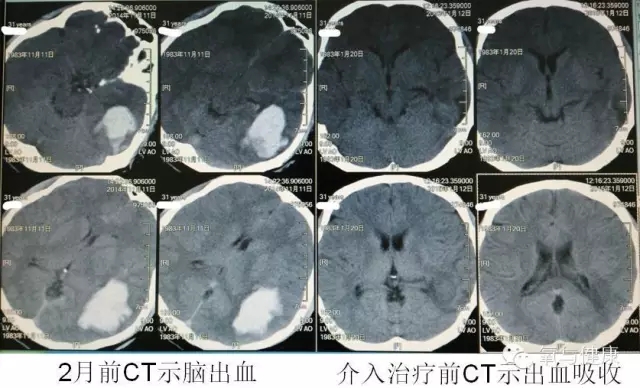

患者男,31岁。主因脑出血后发现颅内动静脉畸形2月入院。患者2月前无诱因突发头痛、恶心,不伴明显肢体麻木无力等神经缺损症状体征。诊断为脑出血。内科治疗后症状减轻,复查头颅CT示出血吸收。头颅MR发现可疑颅内动静脉畸形。行DSA检查证实动静脉畸形。

既往体健。为行介入手术治疗动静脉畸形入院。入院后通过介入术应用聚合胶栓塞畸形血管,术中,导管系统到达基底动脉时,导管破裂,聚合胶进入血流并完全栓塞基底动脉,造成基底动脉急性栓塞,导致患者脑桥、左侧小脑梗死。患者出现昏迷,查体呈去皮层状态。Glasgow评分:共5分,其中:睁眼反应1分,语言反应1分,肢体运动3分。给予改善循环、营养脑细胞、抗感染及呼吸机支持等对症治疗。此后3个月,患者症状无变化,病情无好转。